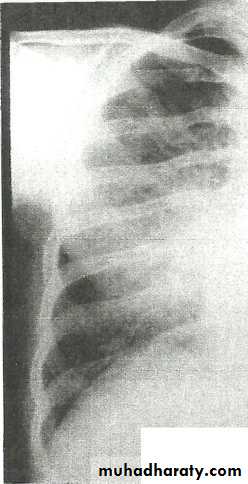

Pleural Effusion on Chest Radiographs.

Posteroanterior (A) and lateral (B) chest radiographs demonstrate the typical meniscoid appearance (arrows) in a patient with a left pleural effusion